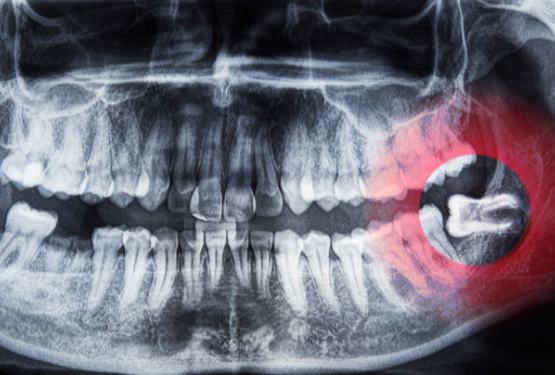

사랑니는 곧게 나오는 경우도 있지만, 대부분 비스듬히 누워있거나 매복된 형태로 맹출합니다. 이러한 형태는 잇몸 염증, 충치, 인접 치아 손상 등 다양한 문제를 야기합니다.